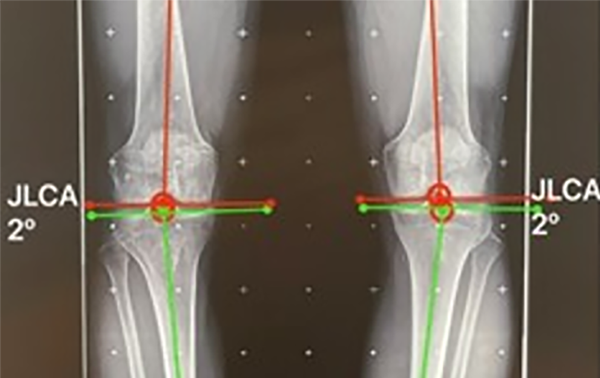

Figura 5: JLCA bilateral de 2° (valor normal 0-2°).